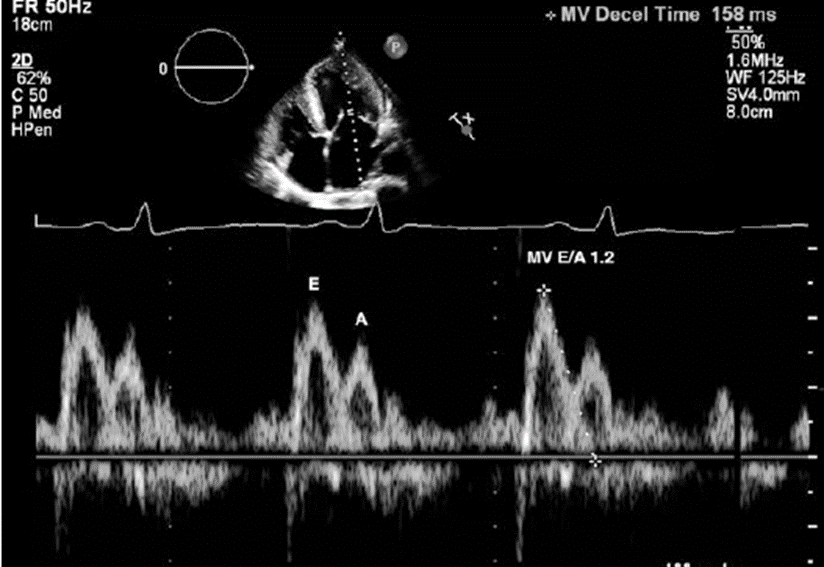

Doppler dòng chảy qua van 2 lá đo 4 buồng từ mỏm tim (A4C) với con trỏe Doppler chỉ ở đỉnh lá van 2 lá [2, 4]. Sóng ban đầu giai đoạn sớm đổ đầy tâm trương đánh dấu là sóng E. sóng thứ 2 tái xuất hiện do nhĩ co đánh dấu là sóng A (Fig. 56.1). ở quả tim bình thường, tỷ số E/A giữa 0,9 và 1,5 [2]. Khi mức độ giãn bị hạn chế

4. Figure 56.1 cho thấy dòng Doppler qua van 2 lá ở bệnh nhân của chúng ta. Hình ảnh 2D (phía trên) cho thấy Doppler PW con trỏ đặt ở đỉnh van 2 lá. Dạng sóng Doppler (bên dưới) cho biết tình trạng đổ đầy thất trái. E là phase sớm đổ đầy tâm trương và A là nhĩ co. Figure 56.2 cho thấy TDI và con trỏ PW Doppler đặt ở giữa (vách) vòng van 2 lá (trái) và thành bên của vòng van (bên phải). e′ (độ giãn cơ tim phase sớm tâm trương) ký hiệu bên dưới dải Doppler. Dữ liệu thu được từ hình Fig. 56.1dùng để tính tỷ số E/e′ trung bình. Figure 56.3 cho thấy tín hiệu CW Doppler TR. Hình ảnh 2D (phía trên) cho thấy xung Doppler qua dòng trào ngược van 3 lá (tín hiệu màu xanh). Vận tốc đỉnh TR được đánh dấu trên dải sóng Doppler. Figure 56.4 cho thấy hình phóng to của nhĩ trái ở hình ảnh 2 buồng tim A2C. LAESVi được tính theo phương pháp Simpson điều chỉnh. Gồm kết hợp với hình ảnh A4C của nhĩ trái nhân thể tích nhĩ trái chia cho BSA để ra LAESVi.

5. Với bệnh nhân của chúng ta, tỉ số E/A là 1.2 (Fig. 56.1). có thể là bình thường hoặc giả bình thường. do đó, chúng ta cần đánh giá tỷ số E/e′ trung bình, vận tốc đỉnh TR và LAESVi. Tỷ số E/e′ trung bình của bệnh nhân này là >14 ở 19.3 m/s (Fig. 56.2). vận tốc đỉnh TR >2.8 m/s ở 4.19 m/s (Fig. 56.3). chỉ số LAESVi >34 mL/m2 ở 66.5 mL/m2 (Fig. 56.4). cả 3 thông số đều bất thường, LAP tăng và bệnh nhân được chẩn đoán rối loạn chức năng tâm trương độ II